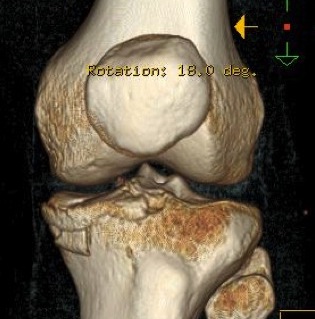

CT demonstrating medial tibial plateau in setting of knee dislocation and posterolateral corner injury